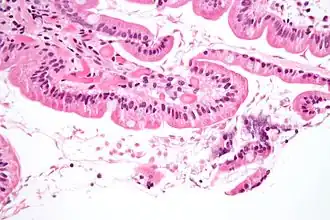

La maladie est due à l’infestation par des protozoaires flagellés : Giardia intestinalis. Les parasites vivent dans l’intestin grêle, à la surface des villosités intestinales. Lors de leur passage dans le côlon, ils se transforment en forme kystique, très résistantes, et sont passivement éliminés avec les selles. Les kystes survivent dans la nature, et vont contaminer un nouvel hôte par ingestion de nourriture ou d’eau contaminée, ou par portage à la bouche de mains souillées. La lambliase est étroitement liée au péril fécal, sa prévalence est corrélée au degré d’hygiène collective et individuelle, au traitement des eaux usées, etc.

Le cycle parasitaire commence par un kyste non infestant éliminé dans les selles d’un individu infecté. Une fois dans l’environnement extérieur, le kyste devient infestant. Un caractère distinctif du kyste est qu’il possède 4 noyaux et un cytoplasme rétracté. Une fois ingéré par l’hôte, le trophozoïte arrive à un stade actif et il est capable de se mouvoir pour trouver sa nourriture. Il se nourrit aux dépens de la muqueuse à l’intérieur du tractus digestif et provoque chez l’hôte des douleurs épigastriques, une distension gazeuse excessive, une diarrhée graisseuse avec du mucus mais pas de sang. Ces symptômes peuvent durer 2 à 4 semaines mais pour un individu intolérant au lactose, les troubles peuvent persister jusqu’à six mois. Après l’étape de prolifération, le trophozoïte subit la phase de reproduction asexuée par scissiparité. Les trophozoites et les kystes résultants de la division traversent alors le système digestif et sont éliminés dans les selles. Les caractères distinctifs des trophozoïtes sont de grands caryosomes et le manque de chromatine périphérique, donnant aux deux noyaux l’aspect d’un halo. C’est une forme primitive de protozoaires à laquelle font également défaut les mitochondries.

Les enfants sont exposés au risque de destruction des villosités digestives, ce qui entraîne un syndrome de malabsorption digestive.